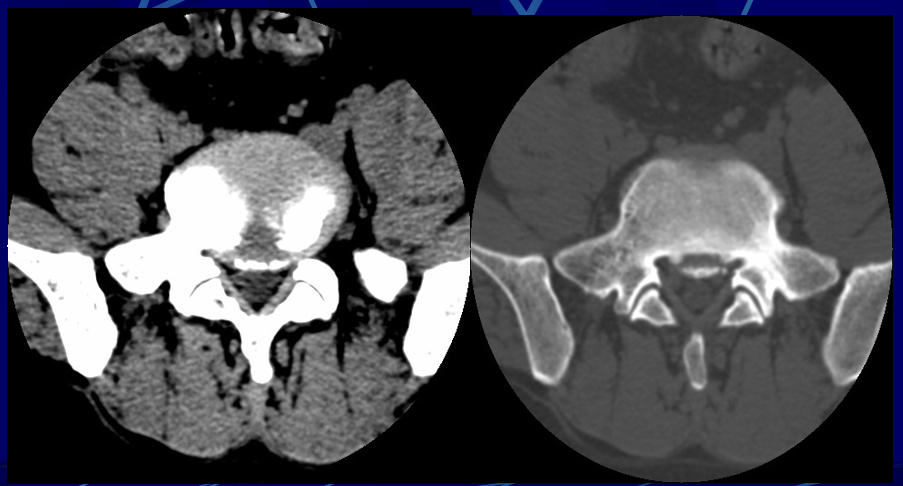

2、椎体后缘软骨结节

• 腰椎后缘软骨结节是椎间盘组织经终板疝入椎体后上部或后下部松质骨内,使腰椎后缘小骨块突入椎管,致椎管狭窄及压迫脊神经根的一种疾病。

• 病理证实除骨块外均系透明软骨和退变的椎间盘组织。

• CT诊断依据::位于椎体上、下的后缘,病灶呈类圆形或多环形的骨缺损,密度与椎间盘相似,周边有反应性骨质硬化,结节的骨性后壁呈弧形凸入椎管,后壁与椎体相连或不连。骨块后缘与突出的腰椎间盘后缘在CT扫描下显示一致,说明骨块是伴随椎间盘同时向椎管内突出的。

椎体后缘软骨结节的发生机理:椎体后缘软骨结节多发生于青少年,  一般认为是青少年时期在解剖缺陷的基础上,在各种应力(主要是纵向挤压)的作用下,特别是伴有屈曲旋转时,髓核的膨胀压力使间盘组织穿过软骨板突入到椎体与骨突环之间的薄弱区,并逐渐扩大形成软骨结节。相邻骨突环受压后移,并继续骨化,形成软骨结节的骨性后壁。部分软骨结节的骨性后壁断裂不连续,少数软骨结节由此突入椎管。

椎体后缘软骨结节多发生于腰骶椎(其中以L5最多,其次S1,再次是由L5向上的各个腰椎,由下向上发病率依次减),极少数发生于不参与胸廓构成的T11、12。颈椎未见发病报告。

根据部位可分为以下几型:(1)上缘正中型:最多见,约占47%,易压迫硬膜囊,较大时可压迫硬膜囊和神经根。

(2)上缘偏侧型:约占25%,易压迫硬膜囊和同侧神经根。

(3)下缘正中型:约占25%,压迫硬膜囊。

(4)下缘偏侧型:很少见,约占3%,压迫硬膜囊及同侧神经根。